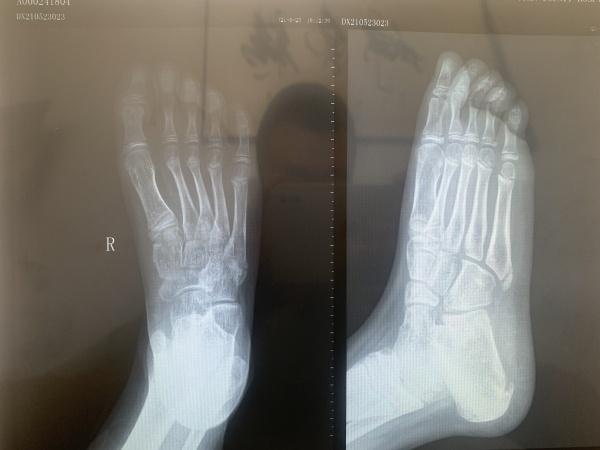

九岁儿童第5跖骨基底部各位大神帮忙看一下

发病一周 有没有手外伤孩子已经表达不清楚,本人考虑骨骺,以前没有遇见过想咨询一下各位大神,这种情况该如何恢复。儿童9岁

分明是右足,为什么会诊断为手外伤,第5跖骨基底部外侧为骨骺而已!

骨骺未愈合。。。。